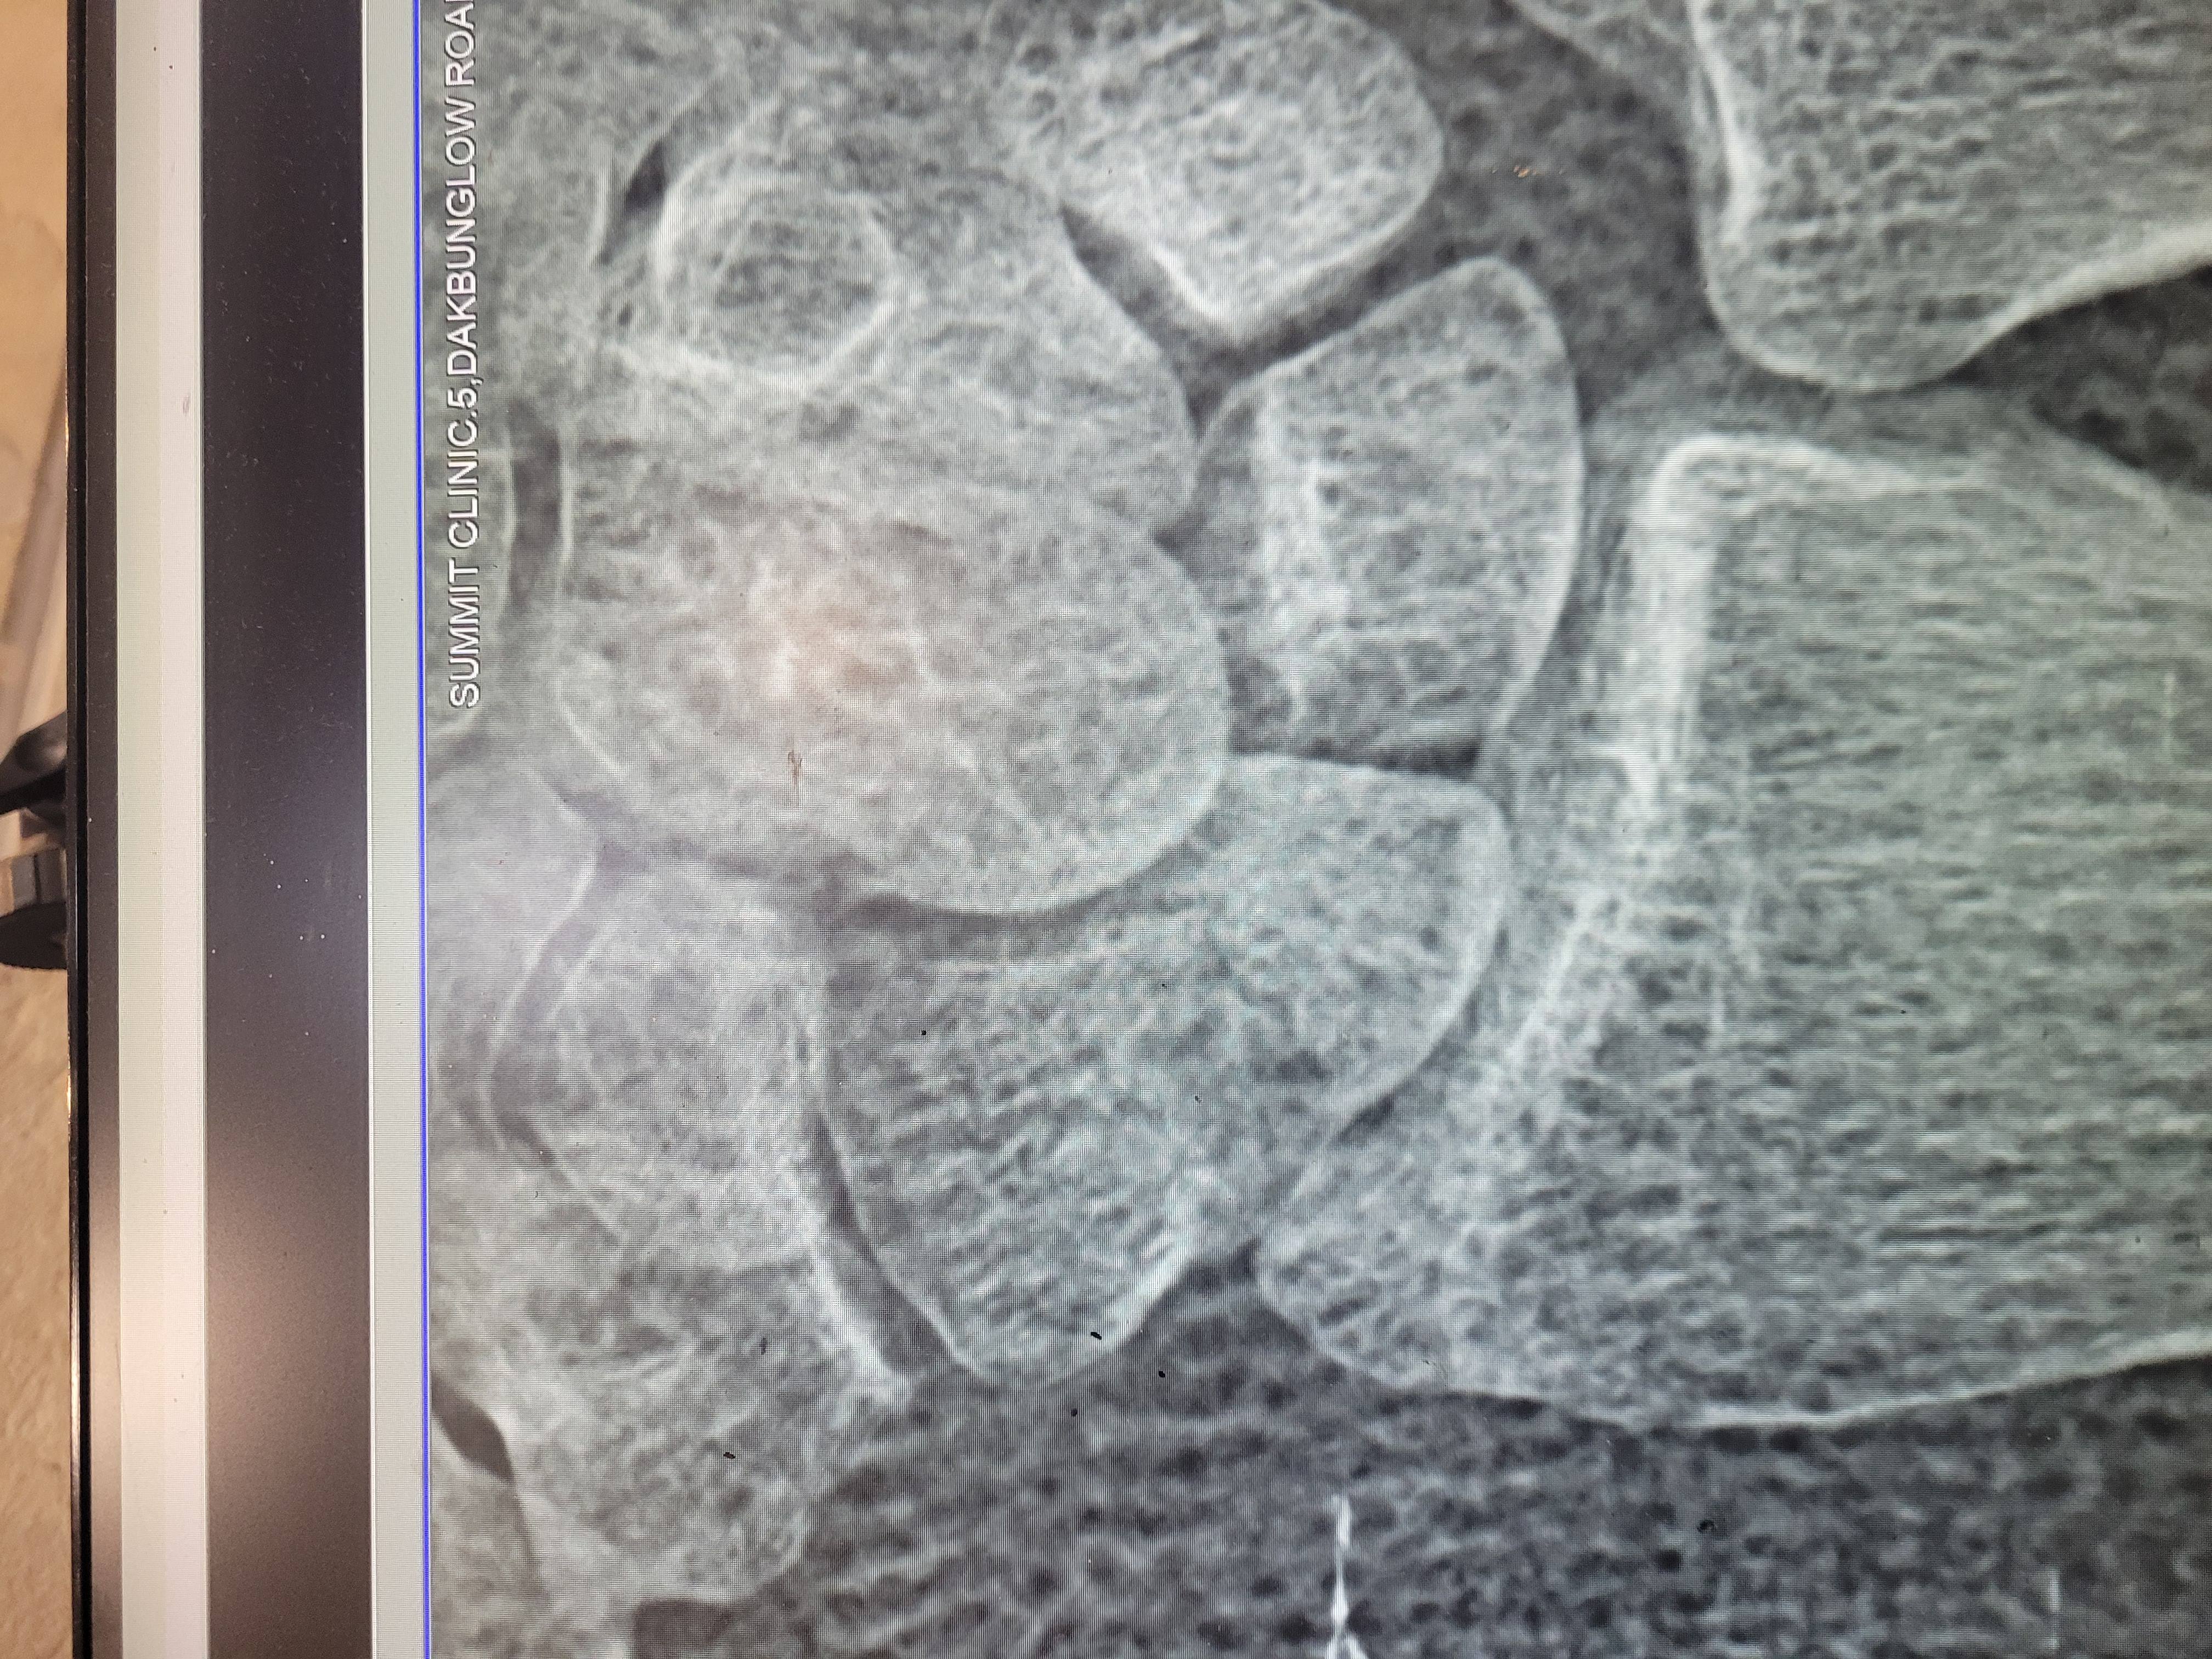

Screw or plaster ?

Scaphiod facture

3 days old facture

Wrist pain

Scaphoid bone pain

Hello sir

I have scaphoid fracture